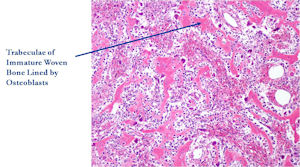

- Interlacing network of bone trabeculae in a loose fibrovascular stroma

- Prominent vessels

- Osteoblasts are plump, active, scattered mitotic figures

- Osteoblasts line up around periphery of trabeculae (Osteoblastic Rimming)

- Soft tissue component usually surrounded by shell of reactive bone or periosteum (Egg Shell Rim of Calcification)

- No cartilage production (as opposed to osteosarcomas that may contain areas of cartilage)